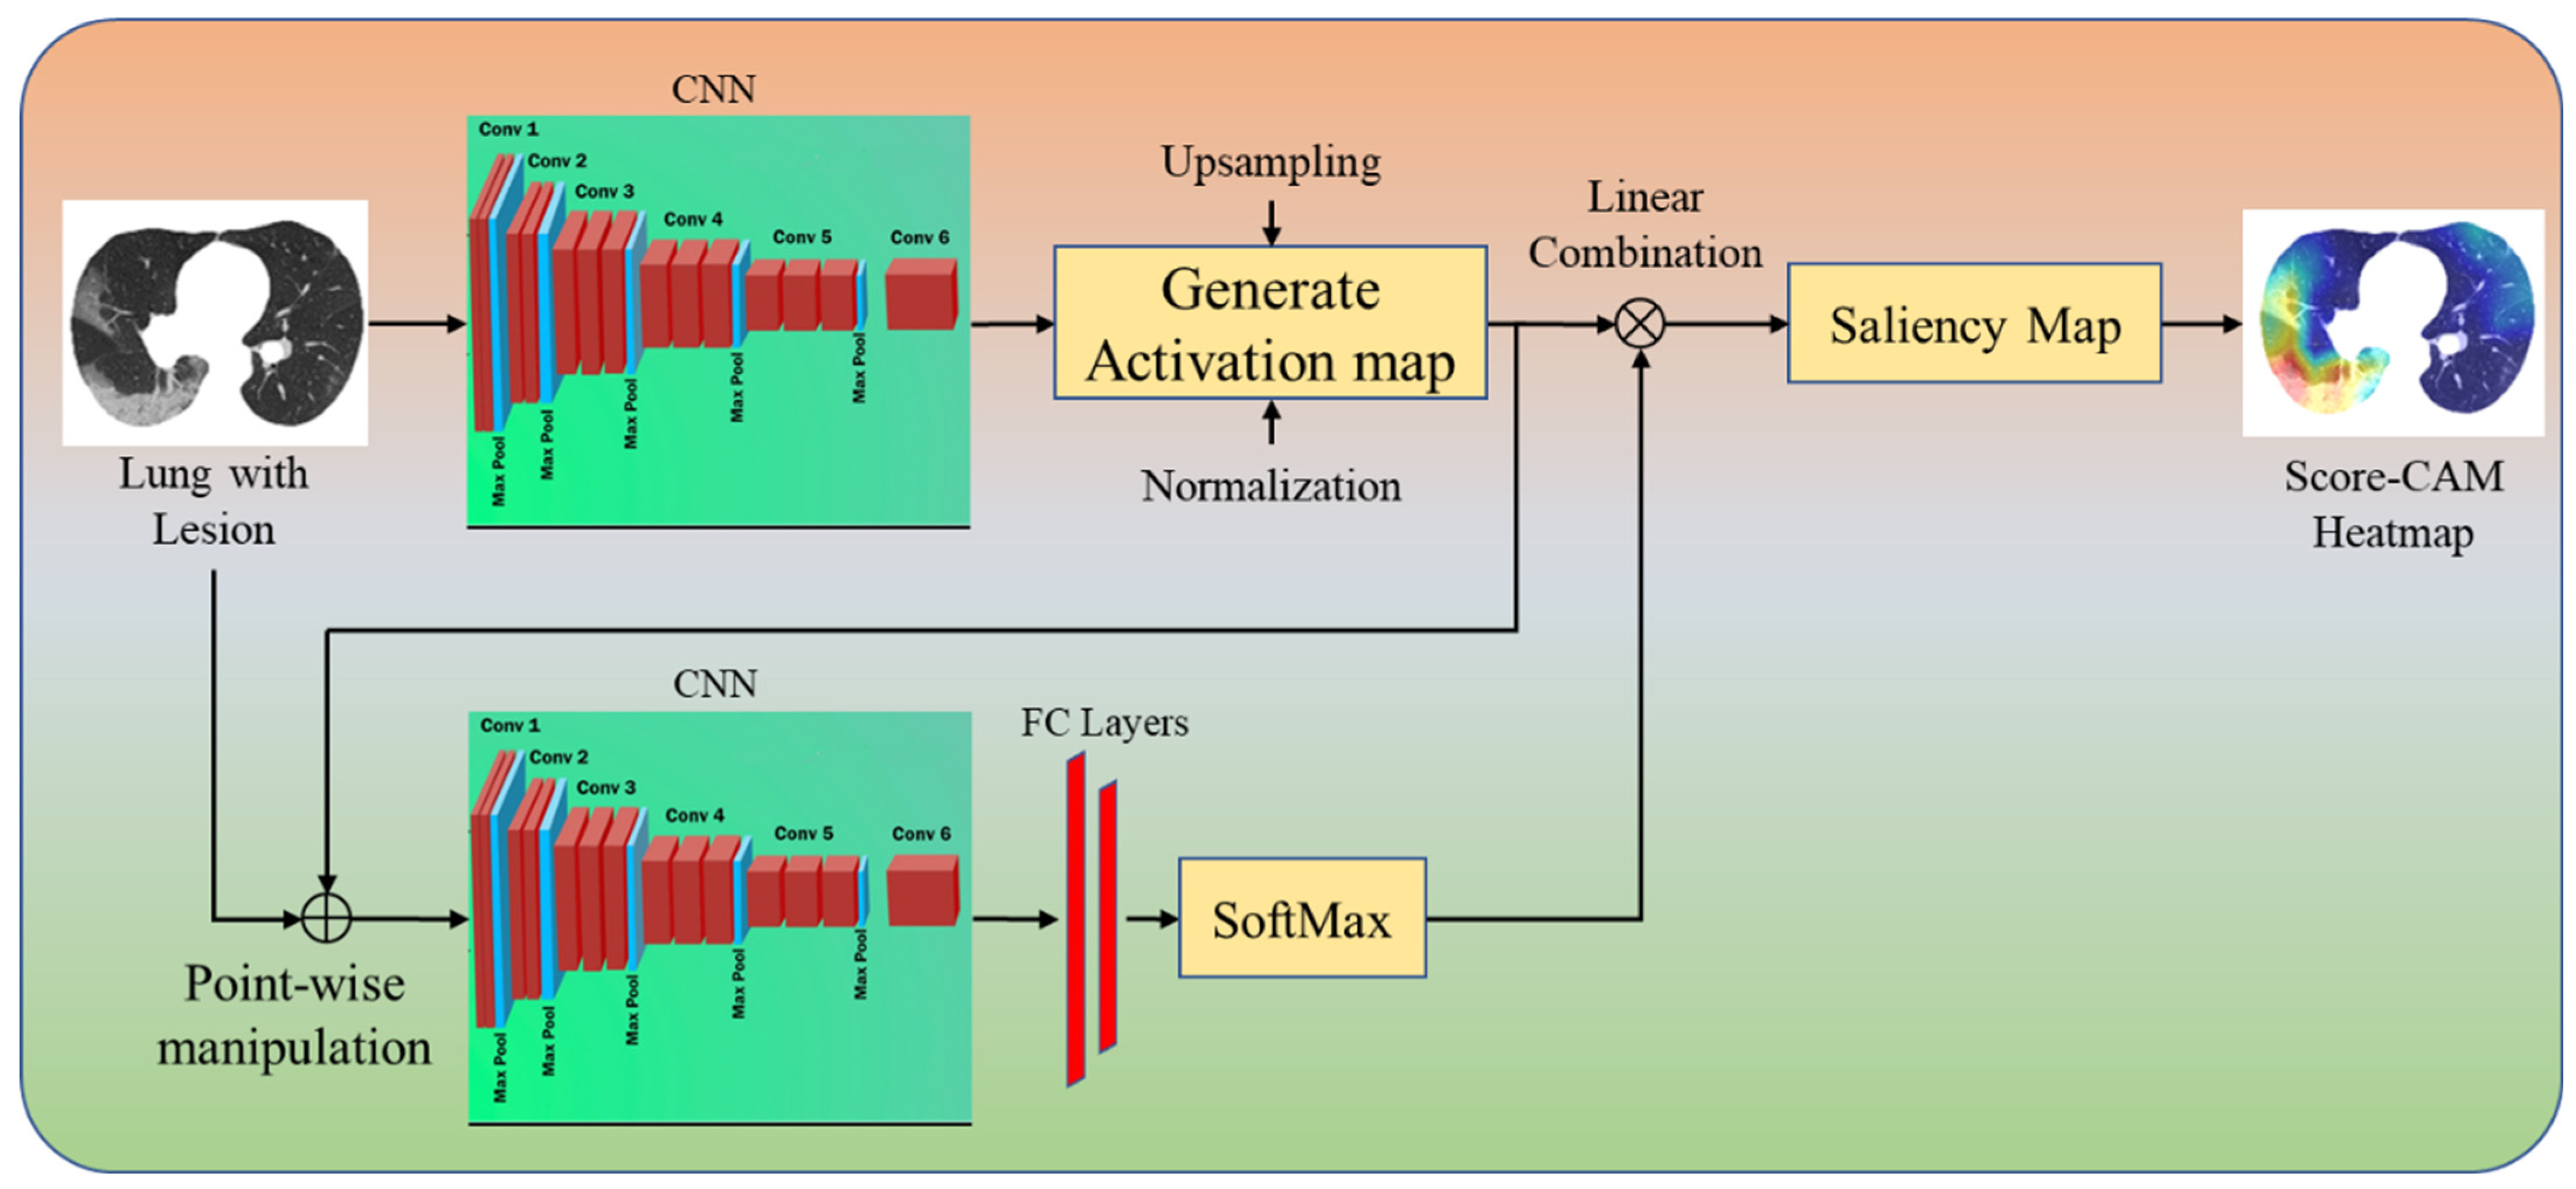

Four CAM Techniques in Cloud-Based Explainable Artificial Intelligence System

4.4. A Special Note on Four CAM Models